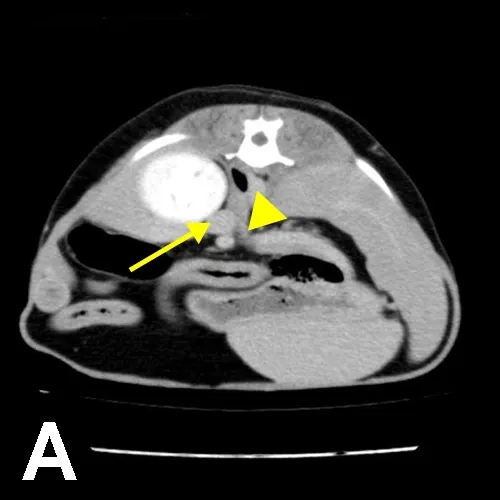

Pheochromocytomas have the potential for vascular invasion and metastasis. The liver and lungs are common sites of metastasis. In all cases, 3-view thoracic radiography should be performed before treatment. Although abdominal ultrasonography is considered an excellent screening tool to evaluate for the presence of adrenal masses and invasion of the vena cava,4 CT is preferred for preoperative planning5 (Figure 1). CT of the thorax and abdomen can determine the extent of disease and evaluate for distant metastasis.

Figure 1. Presurgical CT images of the patient. In the axial view (A), the adrenal mass is visible adjacent to the left kidney (arrow), and extension of tumor into the vena cava is evident (arrowhead). In the coronal view (B), the mass is visible adjacent to the kidney (arrow), but extension into the vena cava is not as obvious.